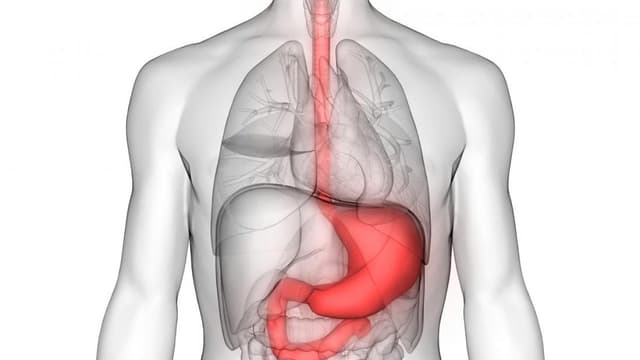

Viêm loét dạ dày chảy máu (hay còn gọi là xuất huyết dạ dày) là một trong những biến chứng nguy hiểm cảnh báo về tình trạng nghiêm trọng của bệnh. Nhận biết sớm các dấu hiệu chảy máu để kịp thời được xử lý và điều trị đúng cách, tránh những hệ quả khôn […]

Xuất huyết tiêu hóa là tình trạng nguy hiểm, có thể đe dọa đến tính mạng người bệnh nếu không được kịp thời phát hiện và điều trị. Bệnh xuất huyết tiêu hóa được chia thành xuất huyết tiêu hóa trên và dưới, có nguyên nhân và các triệu chứng lâm sàng khác nhau. Hãy […]

Bệnh xuất huyết tiêu hóa trên (hay chảy máu đường tiêu hóa trên) là cấp cứu nội ngoại khoa thường gặp hiện nay. Tình trạng này có thể đe dọa đến tính mạng người bệnh nếu không được xử trí kịp thời. Bài viết dưới đây của Hệ thống Y tế Thu Cúc sẽ giúp […]

Hội chứng xuất huyết tiêu hóa dưới chiếm khoảng 20% các trường hợp xuất huyết tiêu hóa. Xuất huyết tiêu hóa dưới là bệnh lý nghiêm trọng, có thể đe dọa đến tính mạng của người bệnh nếu không được phát hiện sớm và điều trị kịp thời, đúng cách. Cùng tìm hiểu về hội […]